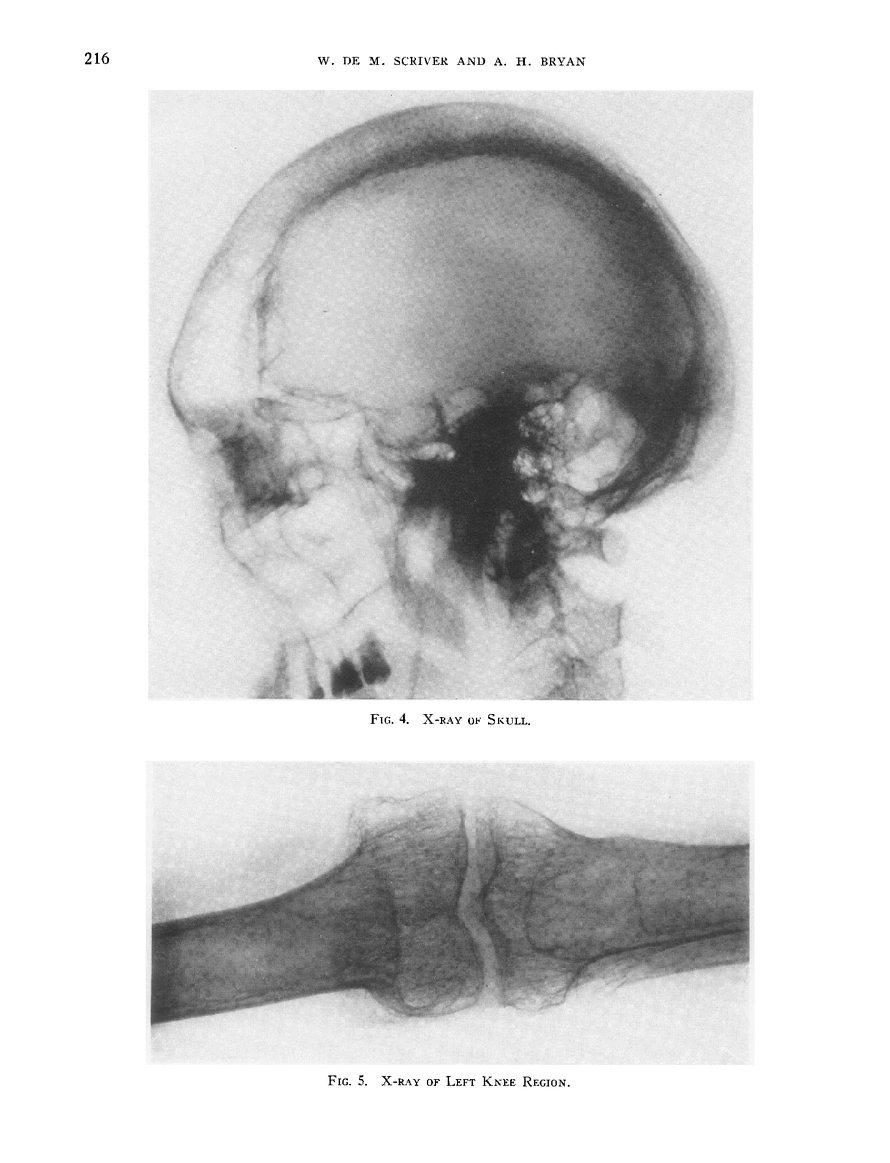

OBSERVATIONS UPON THE CALCIUM AND PHOSPHORUS METABOLISM IN A CASE OF ACROMEGALY SHOWING MARKED OSTEOPOROSIS